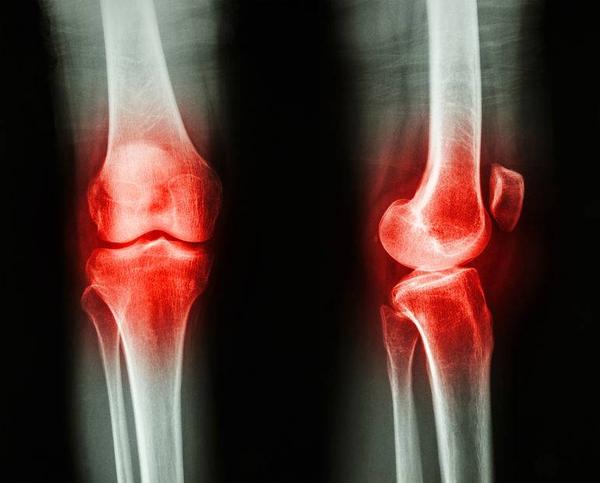

关节炎,顾名思义,就是关节出现了炎症,但是它并不是特指一种疾病。

事实上,造成关节炎性反应的因素有很多,因此关节炎类型在临床上也有许多,比如痛风就是目前我国最为常见、非常复杂的关节炎类型之一。

除此外,类风湿性关节炎,也是一种病因未明确、较为多见的关节炎疾病!

那么问题来了,同样都是关节炎,同样都可能会出现关节肿痛,到底该如何区分这二者呢?